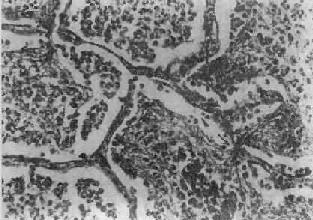

图9-15 大叶性肺炎

肺泡腔内充满纤维素性渗出物,纤维素丝穿过肺泡间孔,使相邻肺泡内的纤维素网互相连接

病变一般发生在单侧肺,多见于左肺下叶,也可同时或先后发生于两个以上肺叶。病变基本特征是肺的微循环障碍。由于毛细血管通透性增高,大量纤维蛋白原渗出于肺泡,使肺组织大面积广泛实变。病变早期,肺叶充血、水肿,肺泡腔内有大量浆液性渗出物,混有少数红细胞、中性粒细胞和巨噬细胞,并含有大量细菌。1~2天后,即有大量纤维蛋白原渗出,肺泡腔内充满混有红细胞、中性粒细胞、巨噬细胞的纤维素性渗出物,纤维素丝可穿过肺泡间孔与相邻肺泡中的纤维素网相连(图9-15)。病变肺叶质实如肝,明显肿胀,重量增加,呈灰白色(图9-16)。如血管损伤较重、出血较多,外观可呈红色。大约经5~10天,炎症消退,细菌被吞噬细胞吞噬清除,渗出物被溶解,或经淋巴管吸收或被咳出。大叶性肺炎时,肺组织常无坏死,肺泡壁结构也未遭破坏,愈复后,肺组织可完全恢复其正常结构和功能。